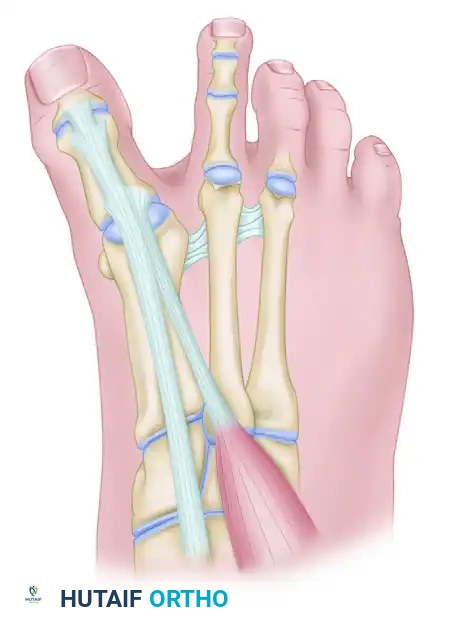

3. Tension the tendon appropriately and secure it with robust nonabsorbable sutures to the adjacent periosteum or directly to the bone using a tenodesis screw or suture anchor, depending on surgeon preference and bone quality.

CORRECTION OF DYNAMIC (MULTIPLANAR) HALLUX VARUS Surgical Diagram

The EHB tendon is pulled through the drill hole under tension and secured with sutures, effectively tethering the proximal phalanx and correcting the varus and extensus deformity.